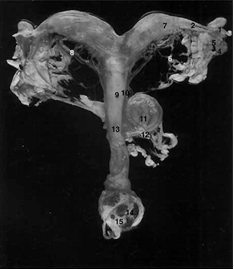

рис. 2. Мочеполовые органы самки

- ректогенитальное углубление; 2 - пузырногенитальное углубление; 3 - уретра; 4 - лоннопузырное углубление; 5 - влагалищное кольцо; 6 - тазовое сращение; 7 - влагалищный вырост брюшины; 8 - жировое тело; 9 - брыжейка матки (мезометрий); 10 - влагалищный вырост брюшины; 11 - круглая связка матки; 12 - параметрий; l3 - периметрий; .14 - матка; 15 - маточная артерия и вена; l6 - внутренний подниматель; 17 - круглая связка матки; 18 - брыжейка матки (мезометрцй); 19 - круглая связка матки; 20 - собственная связка яичника; 21 - брыжейка яичника; 22 - поддерживающая связка яичника; 23 - яйцевод; 24 - рог матки; 25 - поперечное положение двенадцатиперстной кишки; 26 - восходящее положение двенадцатиперстной кишки; 27 - проксимальная брыжейка яичника; 28 - яичниковая артерия и вена; 29 - дистальная брыжейка яичника; З0 - брыжейка яйцевода; 3l - яичник; 32 - яичниковая бурса; 33 - яйцевод; 34 - отверстие яичниковой бурсы; 35 - сосок.

рис. 3. Дорсальная сторона полового тракта суки.

- сумка яичника;

- отверстие сумки яичника;

- поддерживавшая связка яичника;

- яичниковая артерия;

- брыжейка яичника;

- брыжейка матки;

- рог матки;

- маточная ветвь яичниковой артерии;

- тело матки;

- маточная артерия;

- мочевой пузырь;

- мочеточник;

- влагалище;

- вульва;

- половая губа;